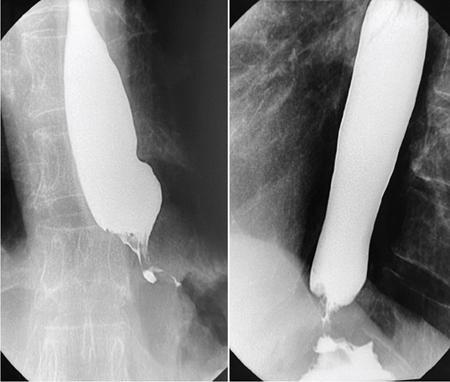

Barium swallow (13 mm tablet/marshmallow/bread soaked in barium) with video fluoroscopy

Inexpensive, easily available

Appropriateness limited on use of spot images and by proficiency/experience of technician/doctor

Can be tailored depending on patient presentation

Negative barium study does not rule out need of endoscopy

Video-fluoroscopy allows adequate/physiological assessment of oesophageal motility

No cross-sectional information obtained

Barium is not absorbed and hence allergic reactions are rare

Barium can elicit severe mediastinitis when used in oesophageal perforations